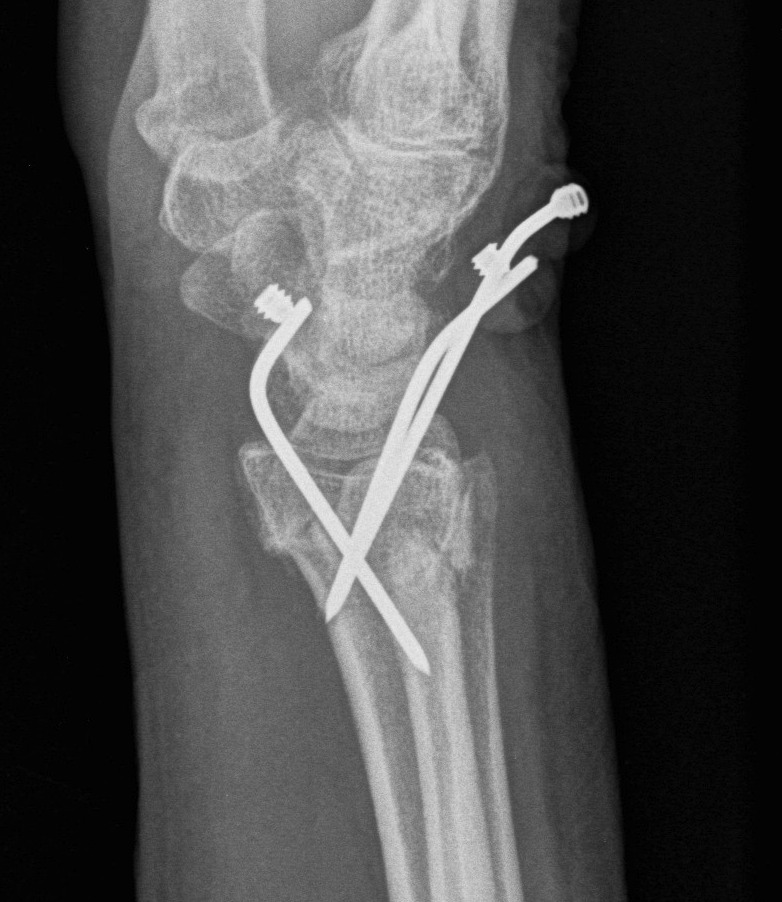

K wires

Distal Radius Fracture K wires APplateex fixbridge plate